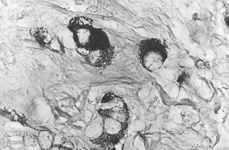

Paciente de treinta y tres años, G3P3, bien reglada, con antecedentes de madre mastectomizada por neoplasia mamaria, que acude a nuestro Servicio remitida por su ginecólogo al presentar una amenorrea de cinco semanas (no debida a gestación) asociada a anexo derecho aumentado al tacto e imagen ecográfica de masa heterogénea quística anexial derecha de 60 x 50 mm, sin excrecencias ni ascitis, que se confirma durante su ingreso. Tras practicar analítica preoperatoria y obtener unos marcadores tumorales (CEA, CA 125, CA19.9, AFP y ß HCG) negativos, se procede a laparotomía, hallando un útero y anexo izquierdo normales, y un quiste ovárico derecho de 6 cm de diámetro, de aspecto anacarado, sin adherencias ni excrecencias en superficie, compatible con teratoma. Se practica lavado para citología peritoneal seguido de anexectomía derecha y cuña de ovario izquierdo. La anatomía patológica solamente muestra en el ovario derecho un teratoma quístico maduro con un tumor carcinoide trabecular en su seno, bien delimitado, sin áreas de extensión (Fig. 1). El lavado peritoneal es negativo para células malignas.

Figura 1.Detalle a gran aumento de células tumorales que muestran abundantes gránulos argentafines, de color negro, intracitoplasmáticos (técnica de Grimelius, x 100).